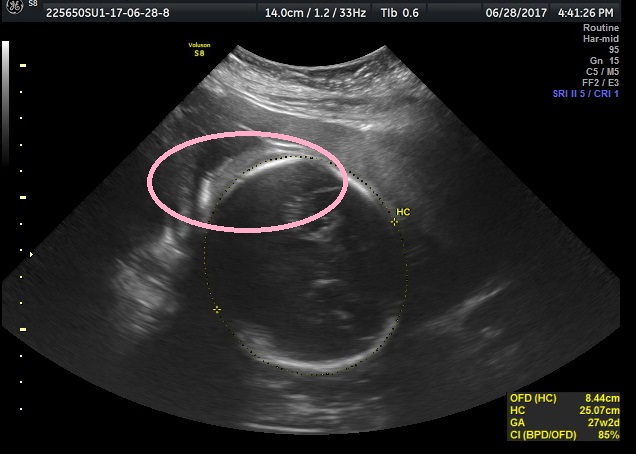

We already know baby is a girl, but I am trying to figure out if this is hair on her head or not? I am hoping this is hair, but it was an elective ultrasound place, and I didn't notice it until after we left so I couldn't ask. Can anyone tell what this is that I circled? Thank you!

Attachment 36898